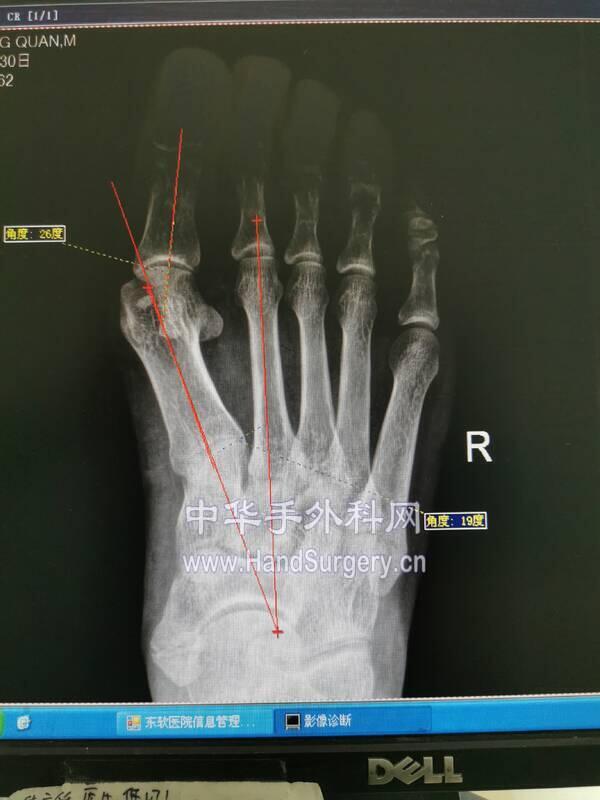

拇外翻角HAA15-20

第一跖骨间角IMA<10

IMG_20200630_155246.jpg